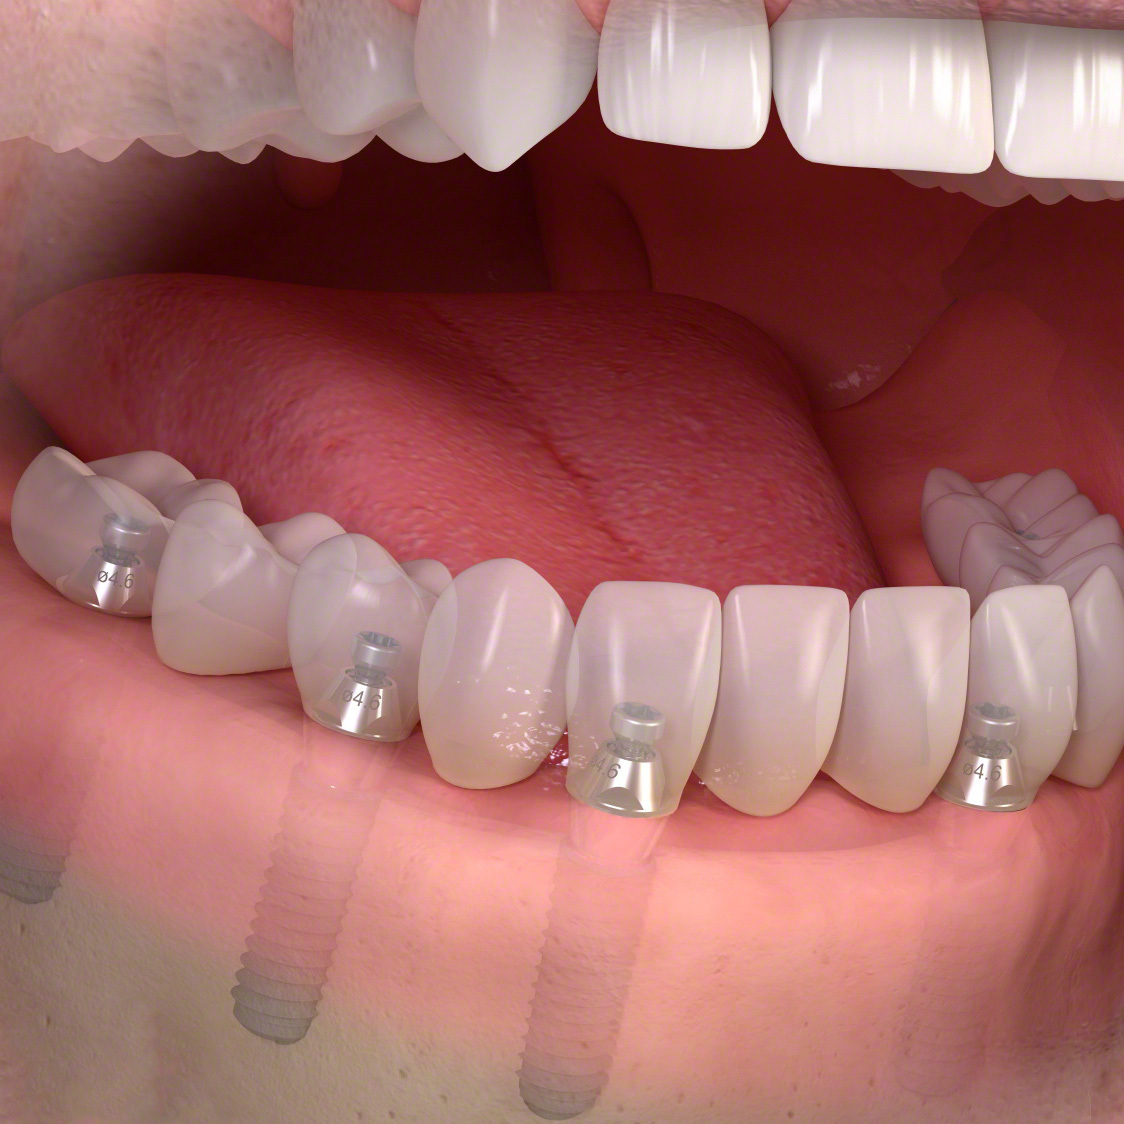

埋入ガイド

CT画像上にて決定した埋入位置で製作された埋入ガイド。正確でスムーズな手術を行えます。

仮歯

埋入位置に合わせた仮歯を製作します。

仮歯装着①

インプラント埋入後、その日に用意していた仮歯を装着します。

仮歯装着②

仮歯をネジ止めして固定します。

これはまだネジ穴を塞いでいない状態です。